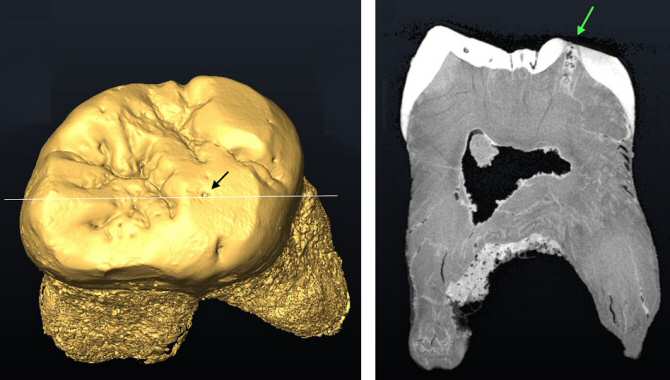

Reconstrucción virtual del diente del Neandertal de El Sidrón con la caries, indicada con una flecha. Imagen: MNCN.

Para evaluar el fósil de la pieza dental dañada, el equipo llevó a cabo análisis químicos no destructivos con un microscopio electrónico de barrido ambiental, que genera imágenes muy detalladas de la superficie del diente y permitió observar la estructura de la caries y analizar los cambios en el esmalte. Mediante tomografía axial computarizada, que permite obtener imágenes en 3D del interior del diente sin dañarlo, se confirmó la presencia de la caries, y se midió su tamaño y profundidad.

El uso de estas técnicas permitió a los investigadores verificar la descalcificación en los bordes de la lesión y la extensión de la misma. Así se consiguió estudiar la caries de forma no destructiva, proporcionando información sobre su origen, desarrollo y relación con la dieta y el comportamiento del neandertal.

“Todo apunta a que el uso intenso de la dentadura pudo provocar una fisura que, poco a poco, fue colonizada por baterías que profundizaron en el esmalte y la dentina hasta desarrollar la caries: una lesión en forma de canal de 2,6 milímetros de longitud”, explica Almudena Estalrrich, investigadora del Museo Nacional del Ciencias Naturales.